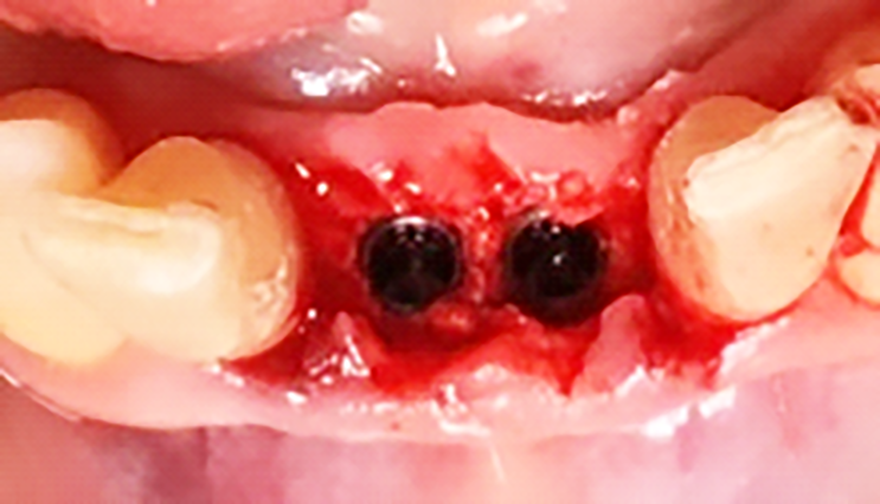

Previa anestesia locale si esegue lo scollamento di un lembo a spessore totale per consentire l’avulsione atraumatica degli elementi 3.1 e 4.1 (figure 1a-1b). Si revisionano le cavità alveolari e si posizionano osso bovino deproteinizzato e una membrana di collagene riassorbibile. Si sutura con filo 5/0, si posiziona un maryland bridge per garantire l’estetica in attesa dell’inserimento implantare e si esegue una radiografia di controllo (figure 2-4).

Dopo 10 mesi, si esegue di un lembo con incisione intrasulculare per gli elementi adiacenti alla sella edentula e festonata sulla sella edentula stessa.

Il lembo viene sollevato a spessore totale sia vestibolarmente che palatalmente (figura 7).

In seguito all’estrazione degli elementi 3.1 e 4.1 si osserva a una settimana di follow up la perfetta guarigione dei siti (figure 4-5). I successivi follow up mostrano come la rigenerativa abbia ristabilito gli adeguati volumi ossei e grazie all’analisi tridimensionale dei siti implantari è possibile pianificare correttamente il posizionamento degli impianti (figura 6).